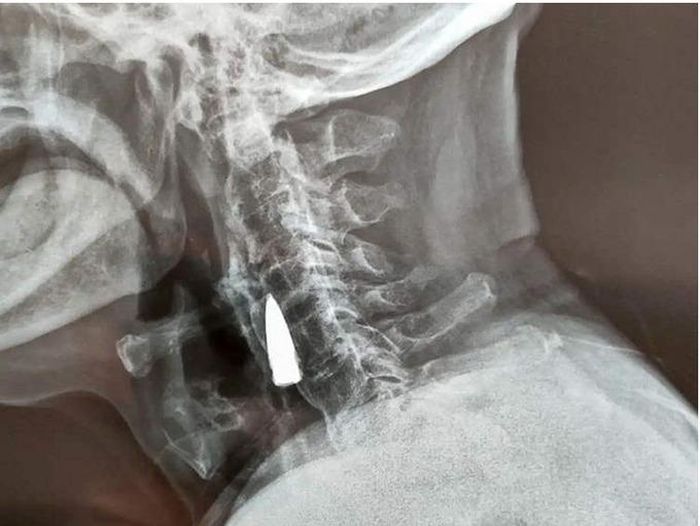

Attached Thumbnails

Click image for larger version

Name:	85691e293264db3a8275.jpg

Views:	0

Size:	47.7 KB

ID:	2139710